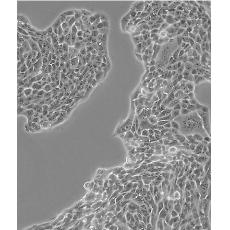

Calu-3

中文名稱 人肺腺癌細胞(胸水)

組織來源 肺腺癌;胸腔積液轉移;男性

生長特性 adherent

形態特征 epithelial